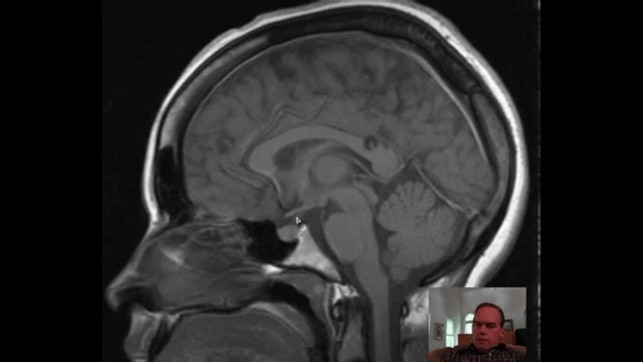

‎请注意,本程式以来自海外的英语放射诊断科视频,提供各种诊断个案,暂时没有提供中/英文字幕。 诊断过程需要优秀的临床技巧,但是,正确应用不同的造影工具,能大大帮助鉴别诊断或证实临床的怀疑。这不应该是”渔翁撒网”式的策略,以一系列的诊断调查表,取代临床技巧。相反,诊断影像的知识,能大大提高诊断过程的水平。 随着科技日新月异,新型医疗仪器不断推陈出新,让医疗专业人员在疾病诊断上,提供极大的帮助。除往日的X光,计算机X射线断层造影术(Computed Tomography, CT),B超(Ultrasound)外,新型的工具包括磁共振显像(MRI),核医学(Nuclear Medicine, NM…